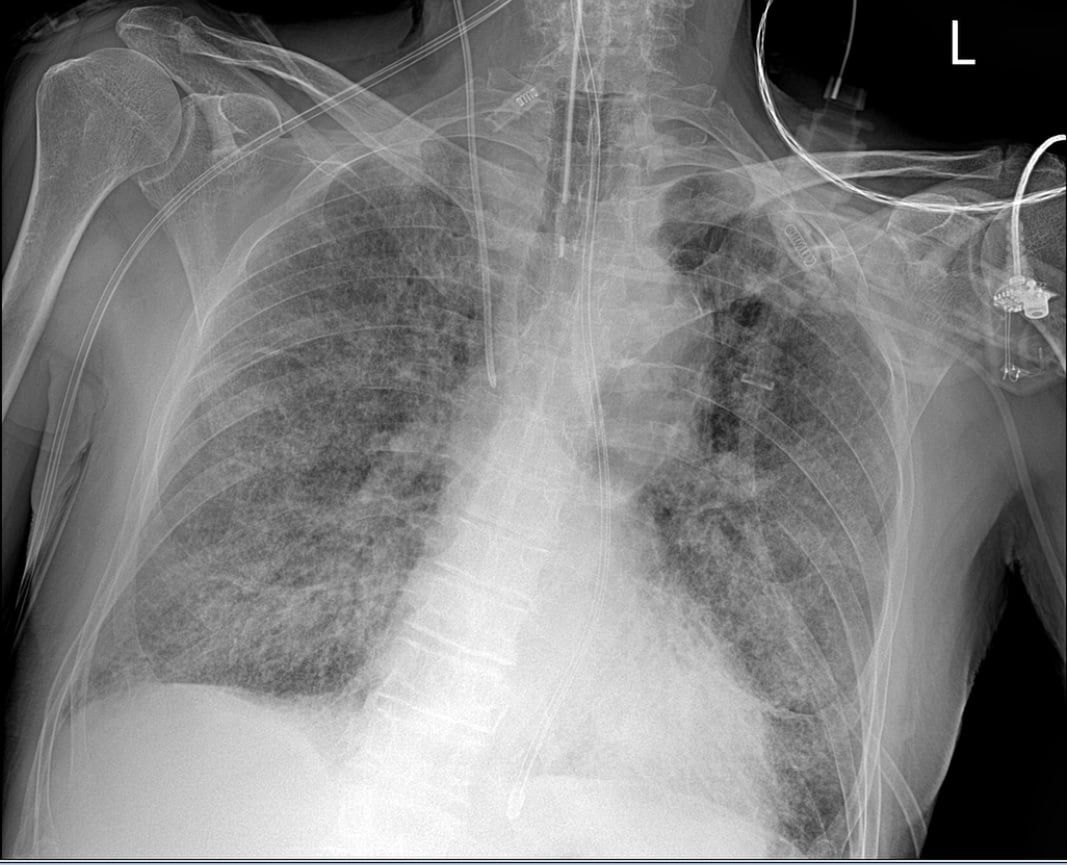

Rezydent opublikował dwie fotografie RTG, które były wykonane u jednego chorego z pozytywnym wynikiem na koronawirusa. "Pierwsze RTG wykonano przy przyjęciu do szpitala, u pacjenta dodatniego z osłabieniem i gorączką, jeszcze bez duszności. Drugie wykonano u tego samego chorego po 7 dniach hospitalizacji, już w skrajnej niewydolności oddechowej wymagającej respiratoroterapii" - opisuje lekarz.

Obraz płuc, w którym 80 proc. powierzchni narządu jest zajęte przez wirusa

Obraz płuc, w którym 80 proc. powierzchni narządu jest zajęte przez wirusa © Tomasz-Rezydent

Wyjaśnia, że ciemnie obszary płuca na pierwszym zdjęciu są w większości z niezmienionej jeszcze chorobowo tkanki, natomiast nakrapiane mlecznie płuca są praktycznie w całości zajęte (odpowiadają 80 proc. zajętego miąższu w tomografii komputerowej).

"Jeden pacjent, siedem dni różnicy. Jeden wredny wirus. Czy miał choroby współistniejące? Tak. Czy to one go zabiły? Nie. Tylko covid" - podsumowuje rezydent.